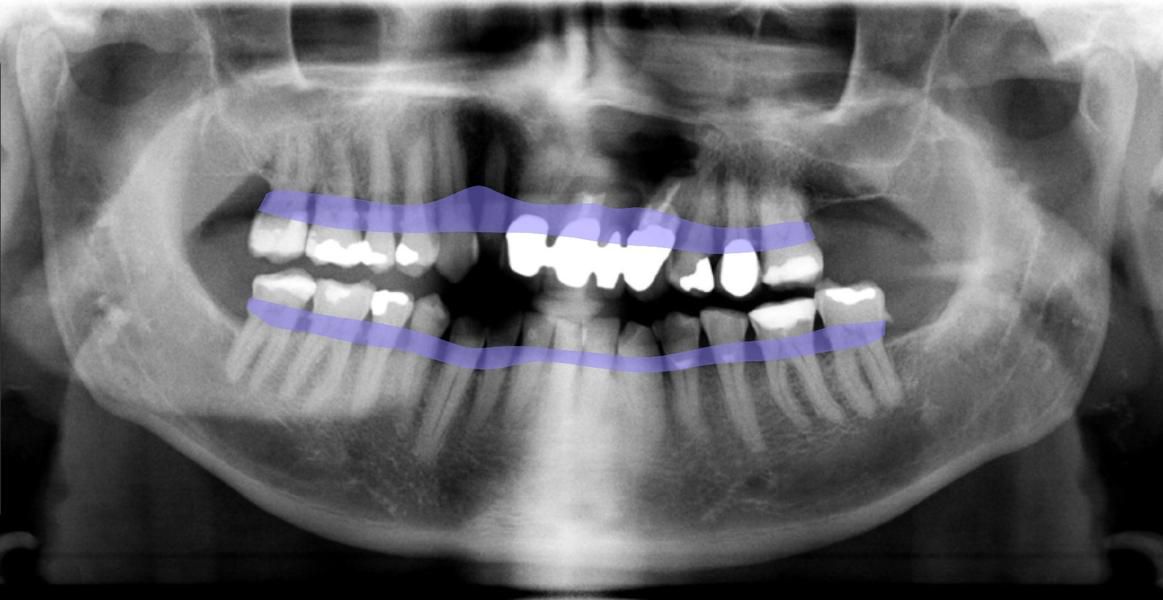

DENTAL XRAI

Zahnarztpraxis Kirste setzt auf künstliche Intelligenz

Technisch ist unsere Zahnarztpraxis stets am Puls der Zeit. Daher freuen wir uns, dass wir jetzt auch zu den Ersten gehören, die bei der zahnmedizinischen Diagnostik auf das KI-unterstützte Tool dentalXrai setzen. Die aus der Berliner Charité entwickelte Software ermöglicht uns eine sichere automatisierte Analyse zahnmedizinischer Röntgenbilder – und zwar in Sekundenschnelle. Die Bestätigung der ärztlichen Befundung durch die KI-Lösung schafft zudem mehr Sicherheit und Vertrauen.

„Mit dem neuen Tool sparen wir nicht nur wertvolle Arbeitszeit, sondern können unsere Patienten noch besser in die Diagnose einbeziehen. Die Röntgenbilder zeigen wir ihnen ab sofort einfach am iPad, das Tool dentalXrai markiert hier Infektionen und Karies farbig. So sind Röntgenbilder und die Diagnose für jedermann leicht zu verstehen“, erklärt ZA Klaus Kirste die Beweggründe, dentalXrai in der Praxis einzuführen.

Die Röntgenbilder können im Anschluss dann einfach als PDF an unsere Patienten versendet werden.